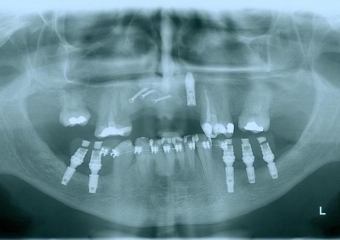

Raio - x implantes inferiores em Junho de 2011  - Clínica Cliniface

Raio - x implantes inferiores em Junho de 2011